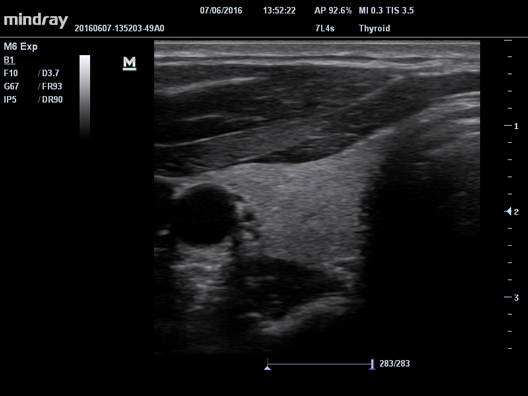

HR Flow

Передовая технология на основе эксклюзивного алгоритма обработки изображений Mindray, обеспечивающая улучшенную визуализацию мельчайших сосудов и сложных структур потока.